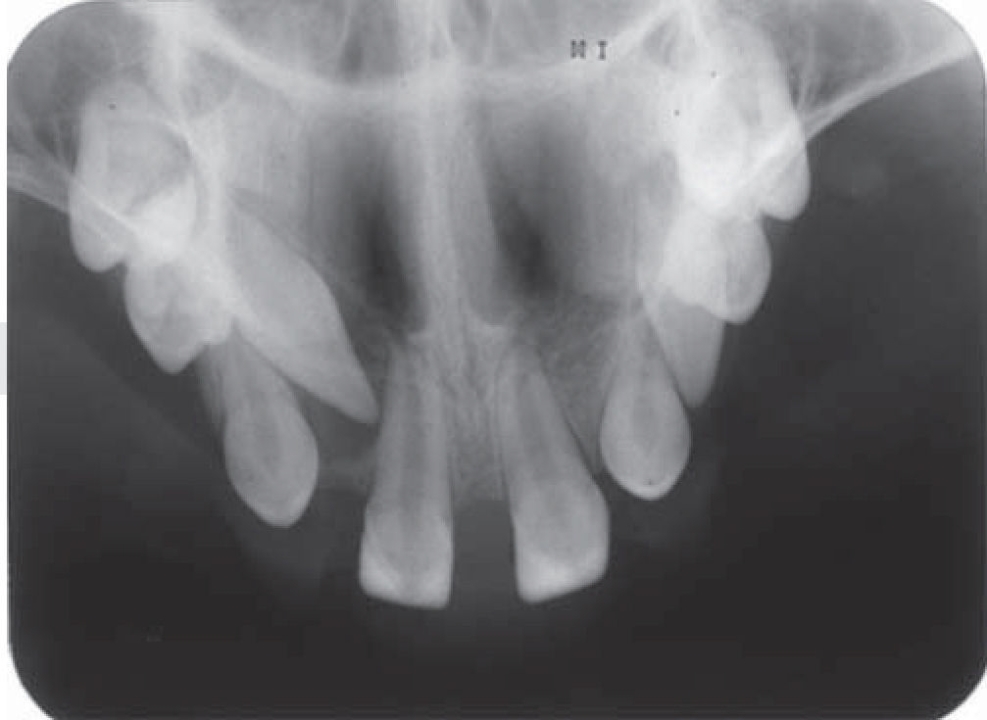

Los exámenes auxiliares más utilizados para este tipo de anomalía son las radiografías panorámicas con el fin de determinar presencia de gérmenes dentarios y anomalías dentarias, observándose dentro de estos últimos oligodoncia, dientes con alteración de forma, principalmente dientes en forma cónica y marcada reabsorción ósea horizontal generalizada. En la mayoría de los casos, los dientes presentes son incisivos superiores, caninos inferiores y superiores, con menor presencia de premolares.2,3,11

El paciente fue sometido a documentación radiográfica inicial, obteniéndose radiografías panorámicas, telerradiografía, oclusal total de maxila (Figuras 2 a 4) (3). En la evaluación radiográfica se observaron agenesias dentarias múltiples, además de las piezas dentarias observadas en el examen intraoral, se presentaban los caninos superiores (derecho e izquierdo) en erupción; germen dentario a nivel del primer premolar superior izquierdo y caninos inferiores en erupción, posiblemente ambos con alteración de forma de la corona dentaria; reabsorción ósea generalizada en ambas arcadas.

Figura 3. Radiografía oclusal de maxila que muestra la disposición de piezas dentarias presentes dentro del arco.

Dentro de los exámenes auxiliares más utilizados para este tipo de alteración están las radiografías extraorales: panorámica y telerradiografía, así también suelen ser usadas radiografías intraorales como la oclusal total y periapical, con el fin de determinar presencia de gérmenes dentarios, reabsorciones óseas, perfil óseo y disposición de piezas dentarias en la maxila como en la mandíbula, con estas referencias la literatura reporta que los dientes permanentes más comúnmente ausentes en individuos portadores de DEH son los incisivos laterales, premolares y segundos y terceros molares. Los dientes más estables son los incisivos centrales superiores, los caninos y primeros molares superiores e inferiores.3,11,13Los incisivos laterales superiores son los dientes inestables comúnmente más ausentes, seguidos de los incisivos centrales inferiores y los dientes más afectados por alteraciones morfológicas son también los incisivos centrales superiores y caninos.14,15El caso que se presenta muestra presencia de los cuatro incisivos superiores con alteración de forma, dientes conoides, caninos superiores en erupción con aparente forma conoide, primeros premolares y primeros molares superiores con taurodoncia, germen dentario del segundo premolar superior izquierdo, ya en la mandíbula se observó la presencia de los incisivos laterales con forma conoide y caninos inferiores en erupción con aparente alteración de forma coronaria de tipo conoide. Se pudo observar también la marcada reabsorción ósea horizontal en ambas maxilas.